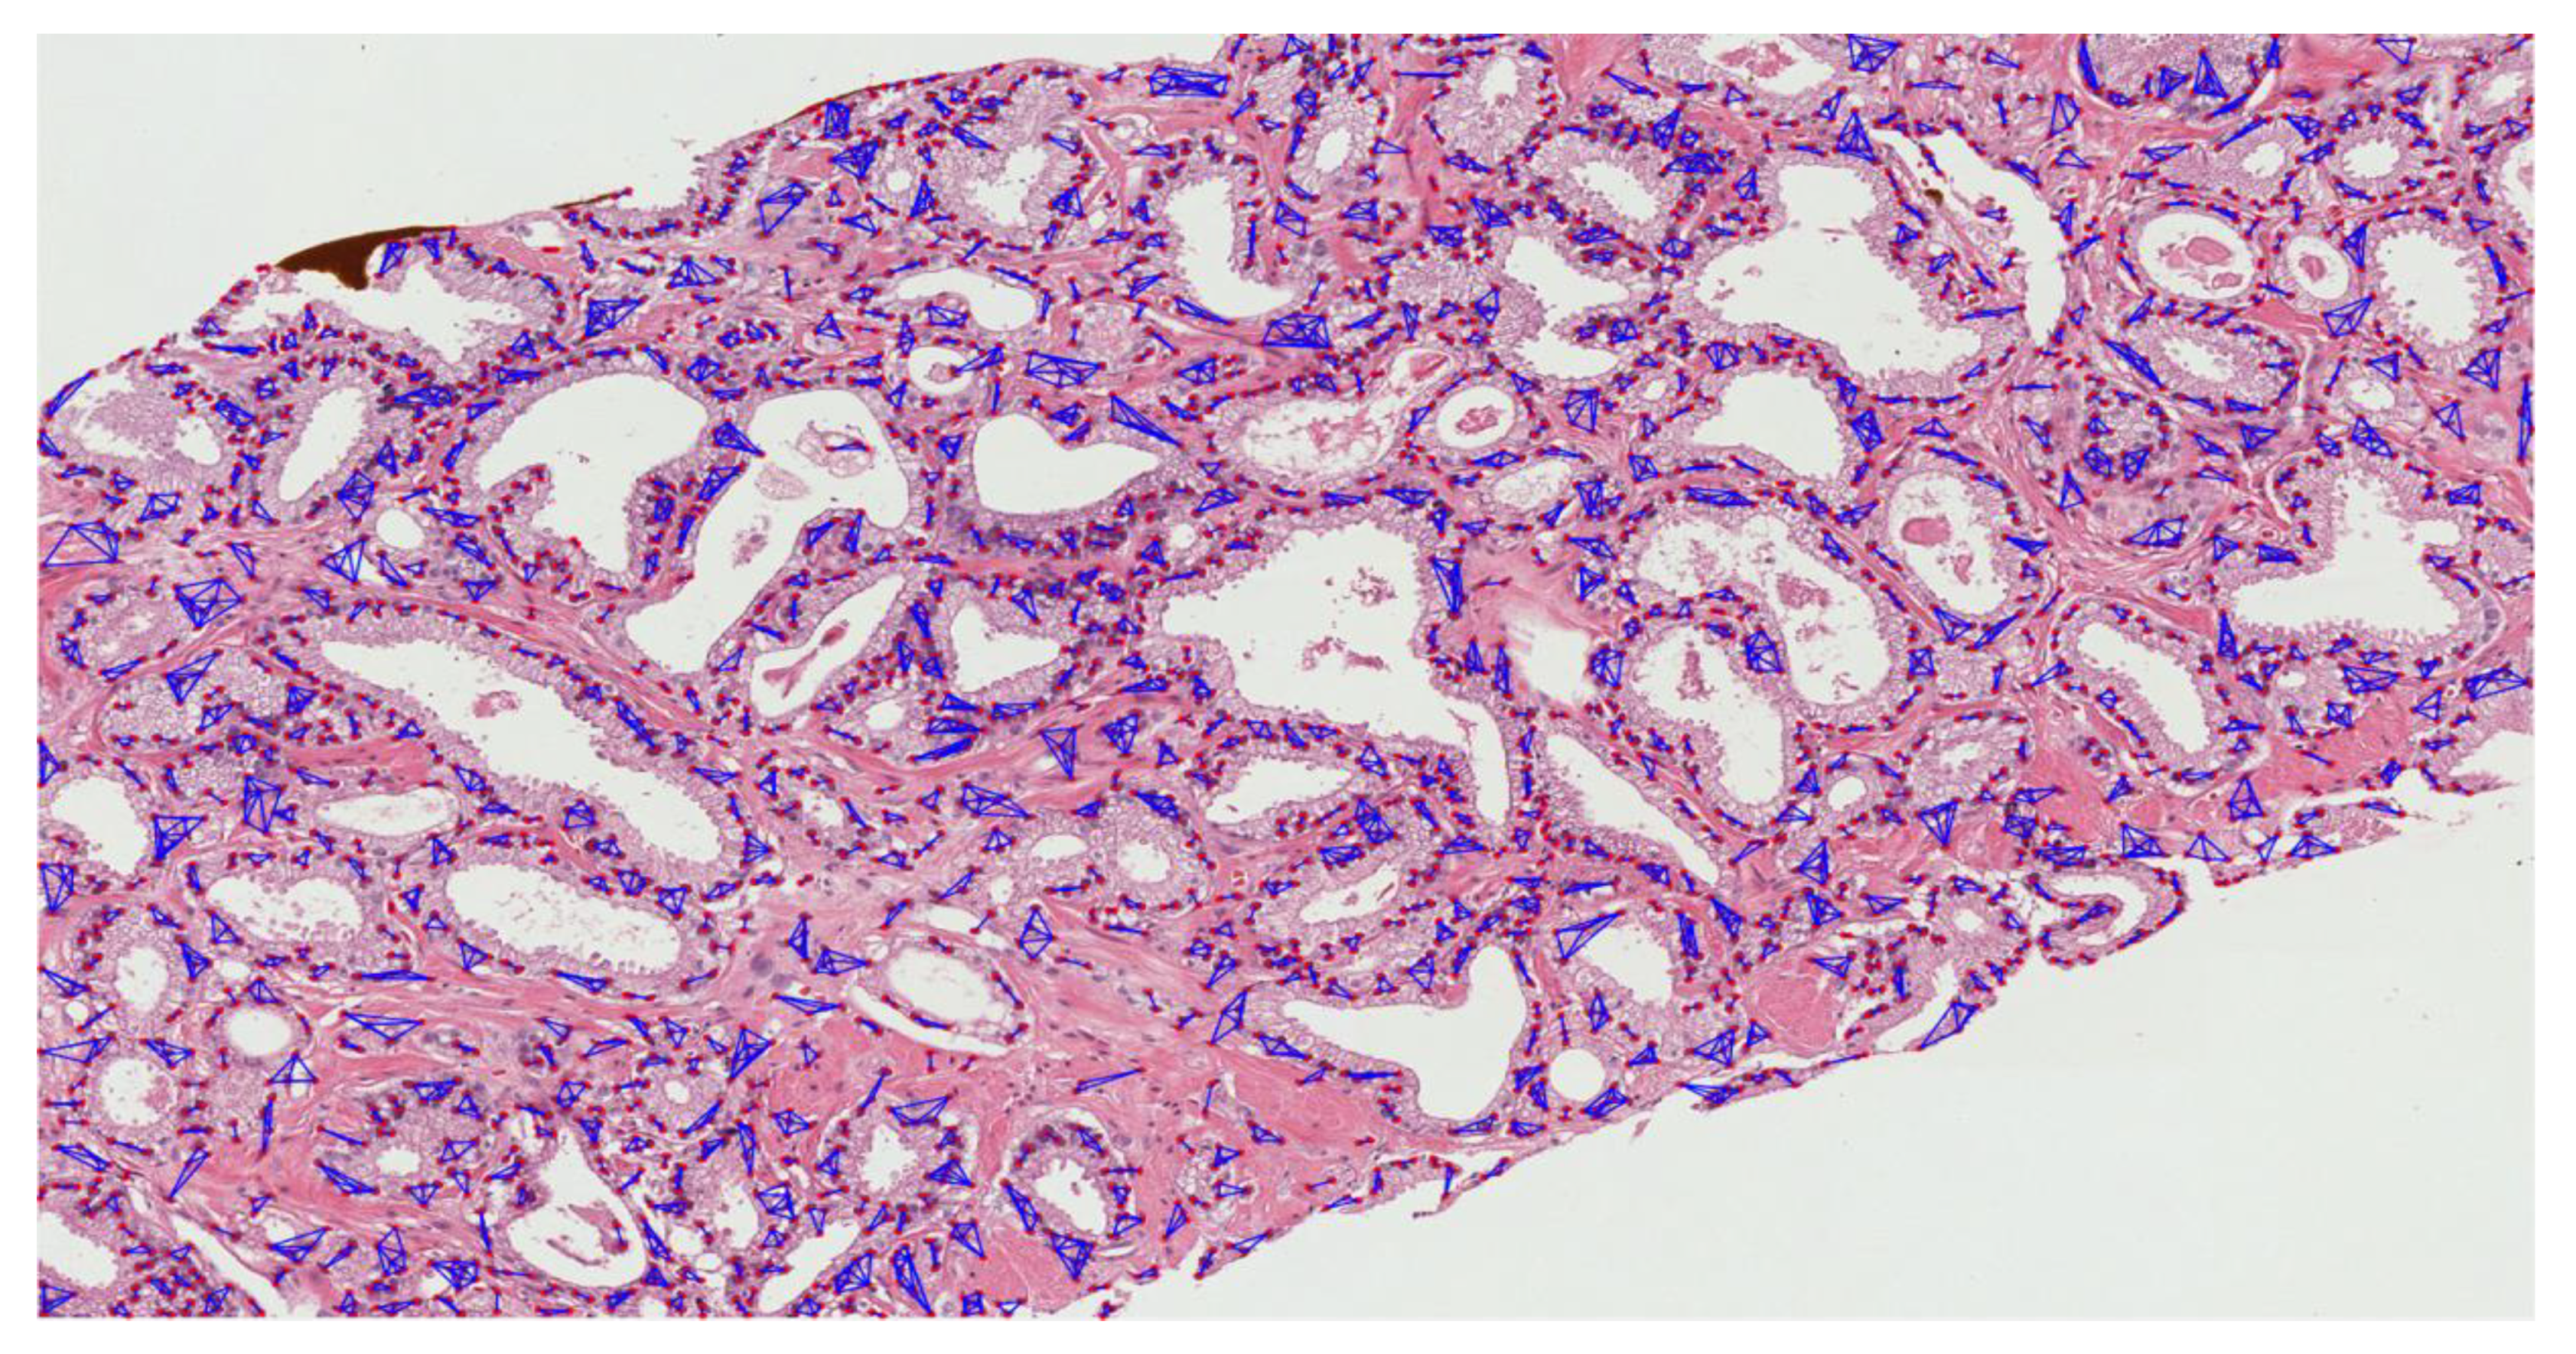

The MST cluster analysis method was applied on the PCa tissue samples of dataset 1 and dataset 2, and the visualization results of intra- and inter-cluster MST are shown in Figure 12. From the following figure, we can analyze that the structure and shape of the clusters in each grade are different from each other. It is quite challenging for researchers and doctors to analyze the microscopic biopsy images of PCa and identify suitable biomarkers compared to other common cancers.

Figure 12.

The visualization of intra- and inter-cluster MST graphs. (a–c) The intra-cluster MST of grade 3, grade 4, and grade 5, respectively. (d–f) The inter-cluster MST was generated from a, b, and c, respectively. The dotted red circle indicates the cluster of cell nuclei. Different color lines in a-c and d-f indicate intra- and inter-clusters, respectively.

The pathology annotated WSIs used in this research to analyze the pattern and community structure of cell nuclei in grades 3, 4, and 5, shown in Figure A1, Figure A2 and Figure A3, respectively. The cluster analysis was performed successfully on histological images of PCa. For visualization of the community structure of cell nuclei, we plot the clusters in the annotated regions of grade 3, grade 4, and grade 5 in WSIs, shown in Figure A4, Figure A5 and Figure A6, respectively.